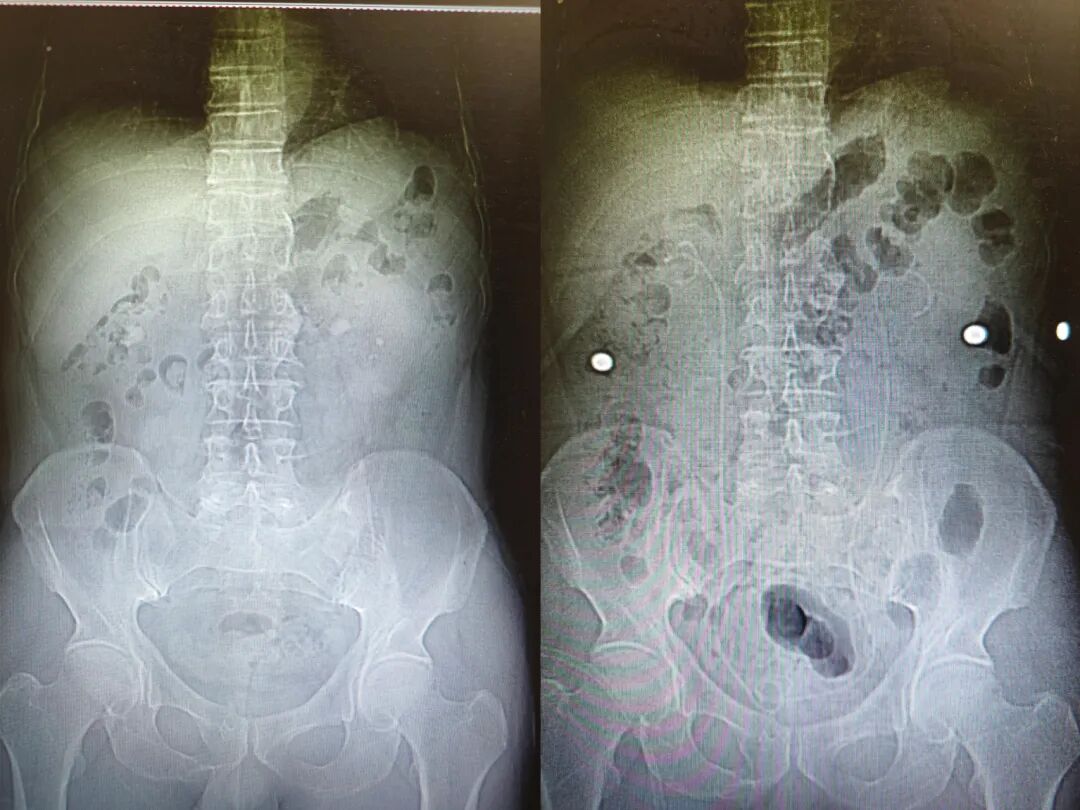

众所周知,肾结石是泌尿外科的常见病和多发病,单个或较小的肾结石治疗相对简单,但复杂性、难治性肾结石几乎都要手术治疗,且往往手术复杂,手术难度和要求都非常高。 近日,我院副院长、泌尿外科主任吴剑平教授成功为一名“双肾结石”患者实施双侧经皮肾镜钬激光碎石手术,患者术后恢复快,手术效果良好。 患者董某,男,55岁,反复腰痛一年余至吴剑平教授专家门诊就诊,经检查确诊为双肾多发结石,门诊拟“双肾结石”收入院治疗。 因患者为双肾多发结石,手术风险和难度较高。患者及家属希望可以通过一次手术解决两侧多发肾结石,这样不仅少受一次创伤,也可大大降低医疗费用。吴剑平教授及泌尿外科团队充分评估了手术风险,在保证患者安全的前提下,制定了详细的手术预案,决定为患者施行双侧经皮肾镜钬激光碎石手术。 手术当天,在麻醉科医师的共同努力下,吴剑平教授手术团队凭借精湛的技术和多年的经验,精细谨慎,历时2小时,顺利将双侧多发的肾结石碎石后取出。目前,患者已康复出院。 我院泌尿外科紧紧跟随国内外泌尿外科发展步伐,坚持以微创为科室发展的主要方向,率先开展了一系列微创治疗新技术,特别是腔镜微创技术的治疗方面取得了骄人成绩。泌尿外科技术团队在多年的发展中,尤其是在东南大学附属中大医院副院长、我院党委书记陈明教授和吴剑平教授的指导下,积累了丰富的泌尿系统疾病的诊治经验,能充分满足临床诊治的需要,未来,泌尿外科将继续以严谨求实的学习态度,一流的技术和优质的服务,为溧水及周边地区泌尿系统疾病患者保驾护航。